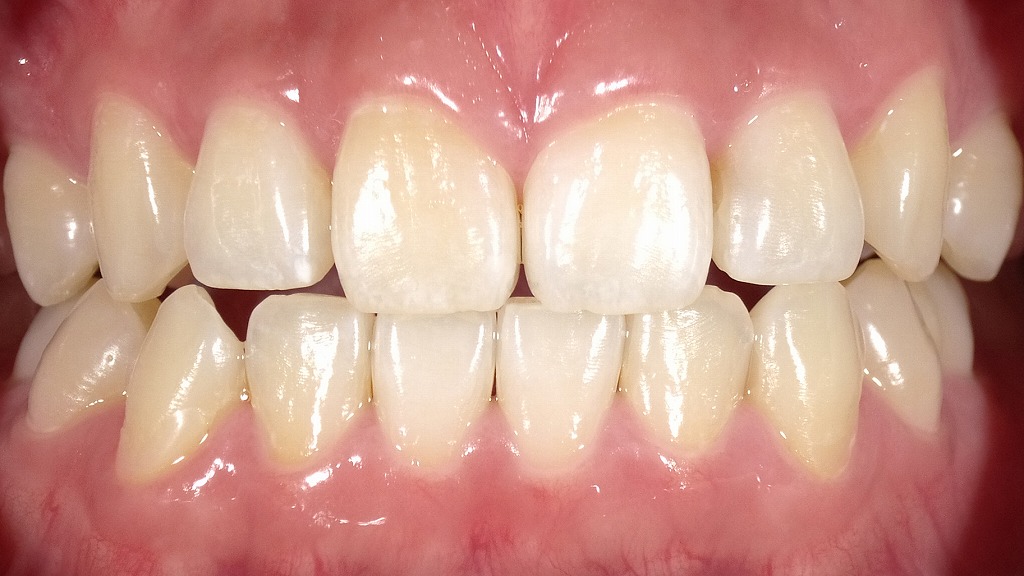

ホワイトニングによりホワイトスポットが目立つようになった症例|術前・術後比較

1枚目の画像:術前

ホワイトニング前の上顎前歯の状態です。

歯の表面に白斑(ホワイトスポット)は存在していますが、歯全体の色調がやや黄味を帯びているため、周囲の歯質とのコントラストが弱く、比較的目立ちにくい状態です。

2枚目の画像:ホワイトニング後

ホワイトニング後の上顎前歯です。

歯全体が明るく白くなったことで、エナメル質内の白斑(ホワイトスポット)が周囲との色差により、以前よりもはっきりと目立つようになっています。

ホワイトニングによって歯が白くなる一方、このようにホワイトスポットが強調されるケースもあります。